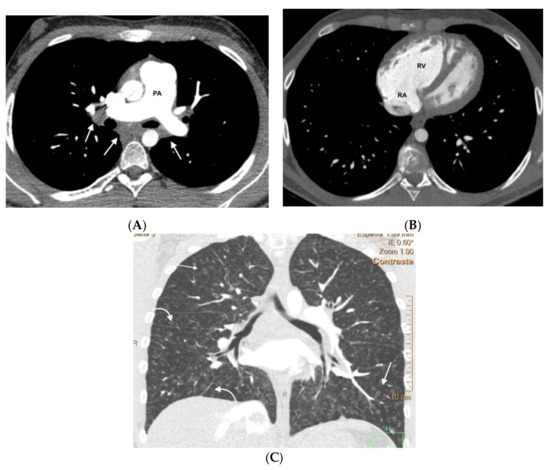

Figure 3.

Fifteen-year-old male with hereditary PVOD and three typical findings of PVOD in MDCT. Radiological signs of pulmonary hypertension: (A) Dilation of the pulmonary artery (PA) trunk and (B) Dilation of the right heart chambers with RV/LV ratio >0.9, hypertrophy of the right ventricular wall, and inversion of the interventricular septum; (C) Extensive involvement in centrilobular nodular ground glass (arrow) and septal lines (curved arrow). Mediastinal lymphadenopathy in subcarinal and bilateral hilar locations (arrows in (A)). PA: pulmonary artery. RA: right atrium. RV: right ventricle.